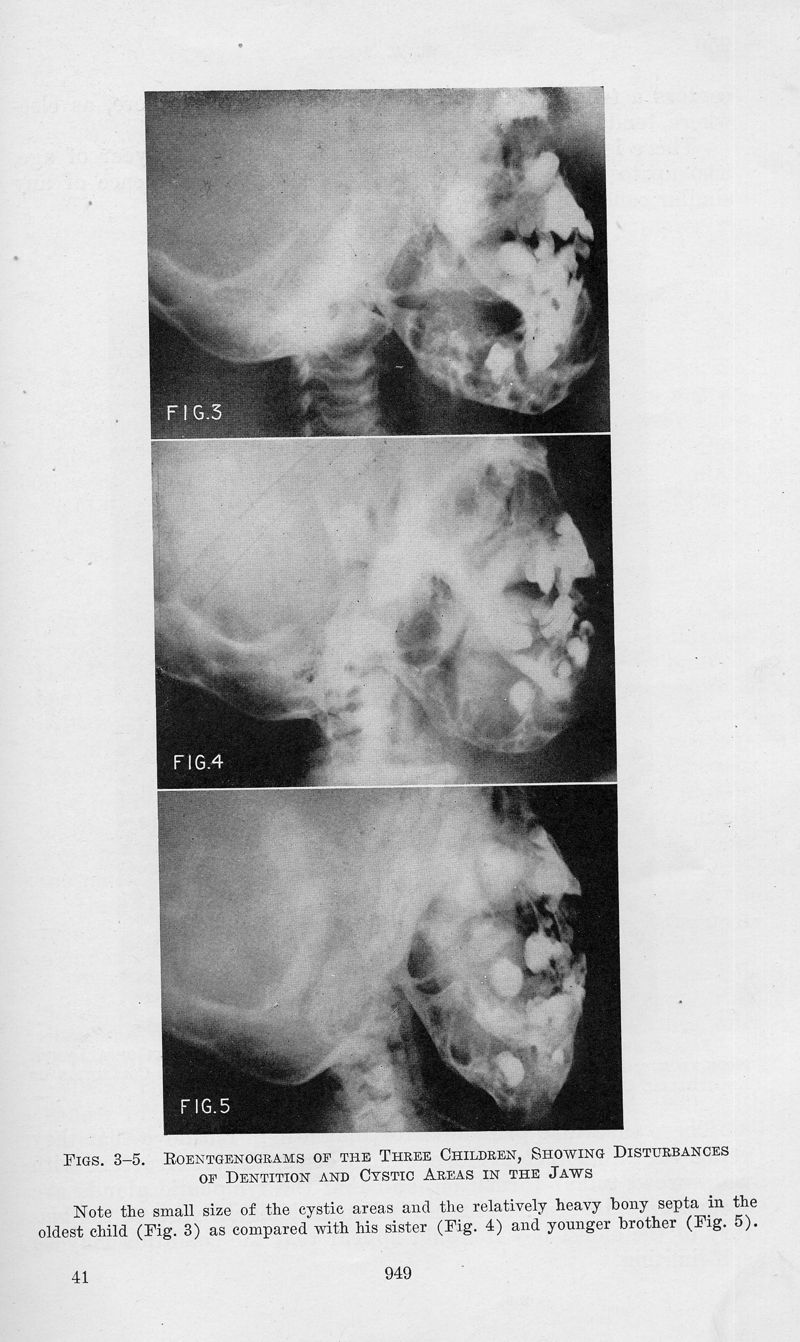

In : [The] American journal of cancer, 1933, Vol. 17, pp. 946-50